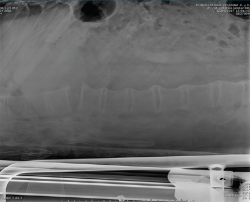

En la Figura 3 puede verse un corte sagital de la TAC cervical con sindesmofitosis también a este nivel, provocando un verdadero canal estrecho cervical en el raquis cervical alto.

Figura 3. Corte sagital de tomografía axial computarizada cervical.